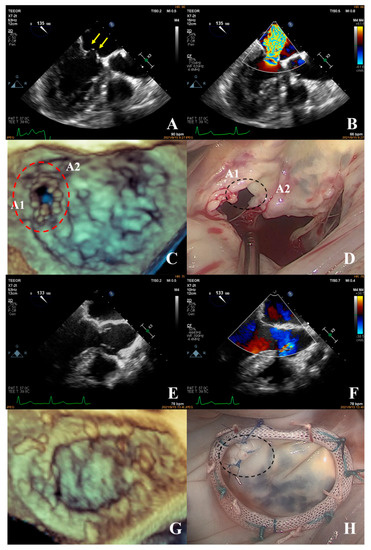

- The fourth case was an unsuccessful mitral valve repair that was converted to mitral valve replacement (Figure 10). The patient had rheumatic valvular disease, with thickened leaflets, restricted leaflet mobility, thickened and shortened sub-valvular chordae tendineae, and commissural fusion observed on three-dimensional images. The complexity score was 8 (1 + 3 + 2 + 2). According to the surgeon’s experience, mitral valve repair was expected to be performed, but the surgical effect was not satisfactory and the patient required a second bypass run. After resuscitation, the intraoperative TEE examination showed that the function of the artificial valve was good.